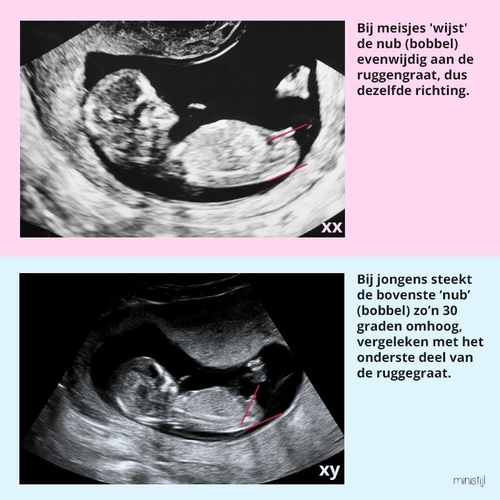

Omdat er zoveel topics over de Nub worden geopend, hebben we 'het grote nub-topic'. Daar kan je je foto plaatsen. Dit topic zal ik sluiten. Succes! 😊